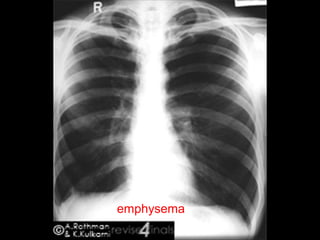

Emphysema

1) EMPHYSEMA

2) B/L PNEUMOTHORAX

3) LARGE MULTIPLE BULLAE

4) B. ASTHMA

5) OVER EXPOSED FILM